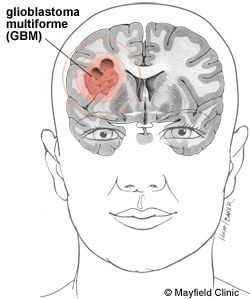

Información: Glioblastoma multiforme. Representa el 25% de todos los tumores cerebrales, el 55% de los tumores del grupo glioma, el 90% de los gliomas de los hemisferios cerebrales del adulto. La punta de incidencia es la edad media de la vida. Hombres doble que mujeres.

Se trata de un tumor altamente maligno muy infiltrante que puede alcanzar un enorme tamaño antes de que llame la atención médica. Puede extenderse hasta la superficie meníngea o pared ventricular. Las células malignas trasportadas por el LCR, pueden formar focos distales en las raices espinales o causar una amplia gliomatosis meníngea. Las metástasis extraneurales son muy raras generalmente afectan al hueso y ganglios lenfáticos después de la craneotomía. Cerca del 50% son bilaterales o ocupan más de un lóbulo o hemisferio. Entre el 3 y 6% son multicéntricos.

Clínicamente, los síntomas cerebrales difusos y convulsiones (presentes en el 30-40% de los casos) dan paso en pocas semanas a un sindrome más definido frontal, parietal, temporal o callosal. Raramente sin embargo los síntomas apuntan a un solo lóbulo cerebral y basta con apuntar a la región amplia que se encuentra involucrada. McCabe observa que el 10% de los glioblastomas comienzan con síntomas mentales confirma nuestra propia experiencia.